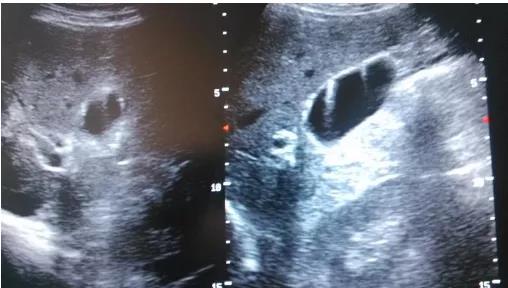

①看真假:真正可能變癌的是真息肉,假息肉不用管;

②看大小:長到1厘米了就需要考慮手術(shù),風險大了;